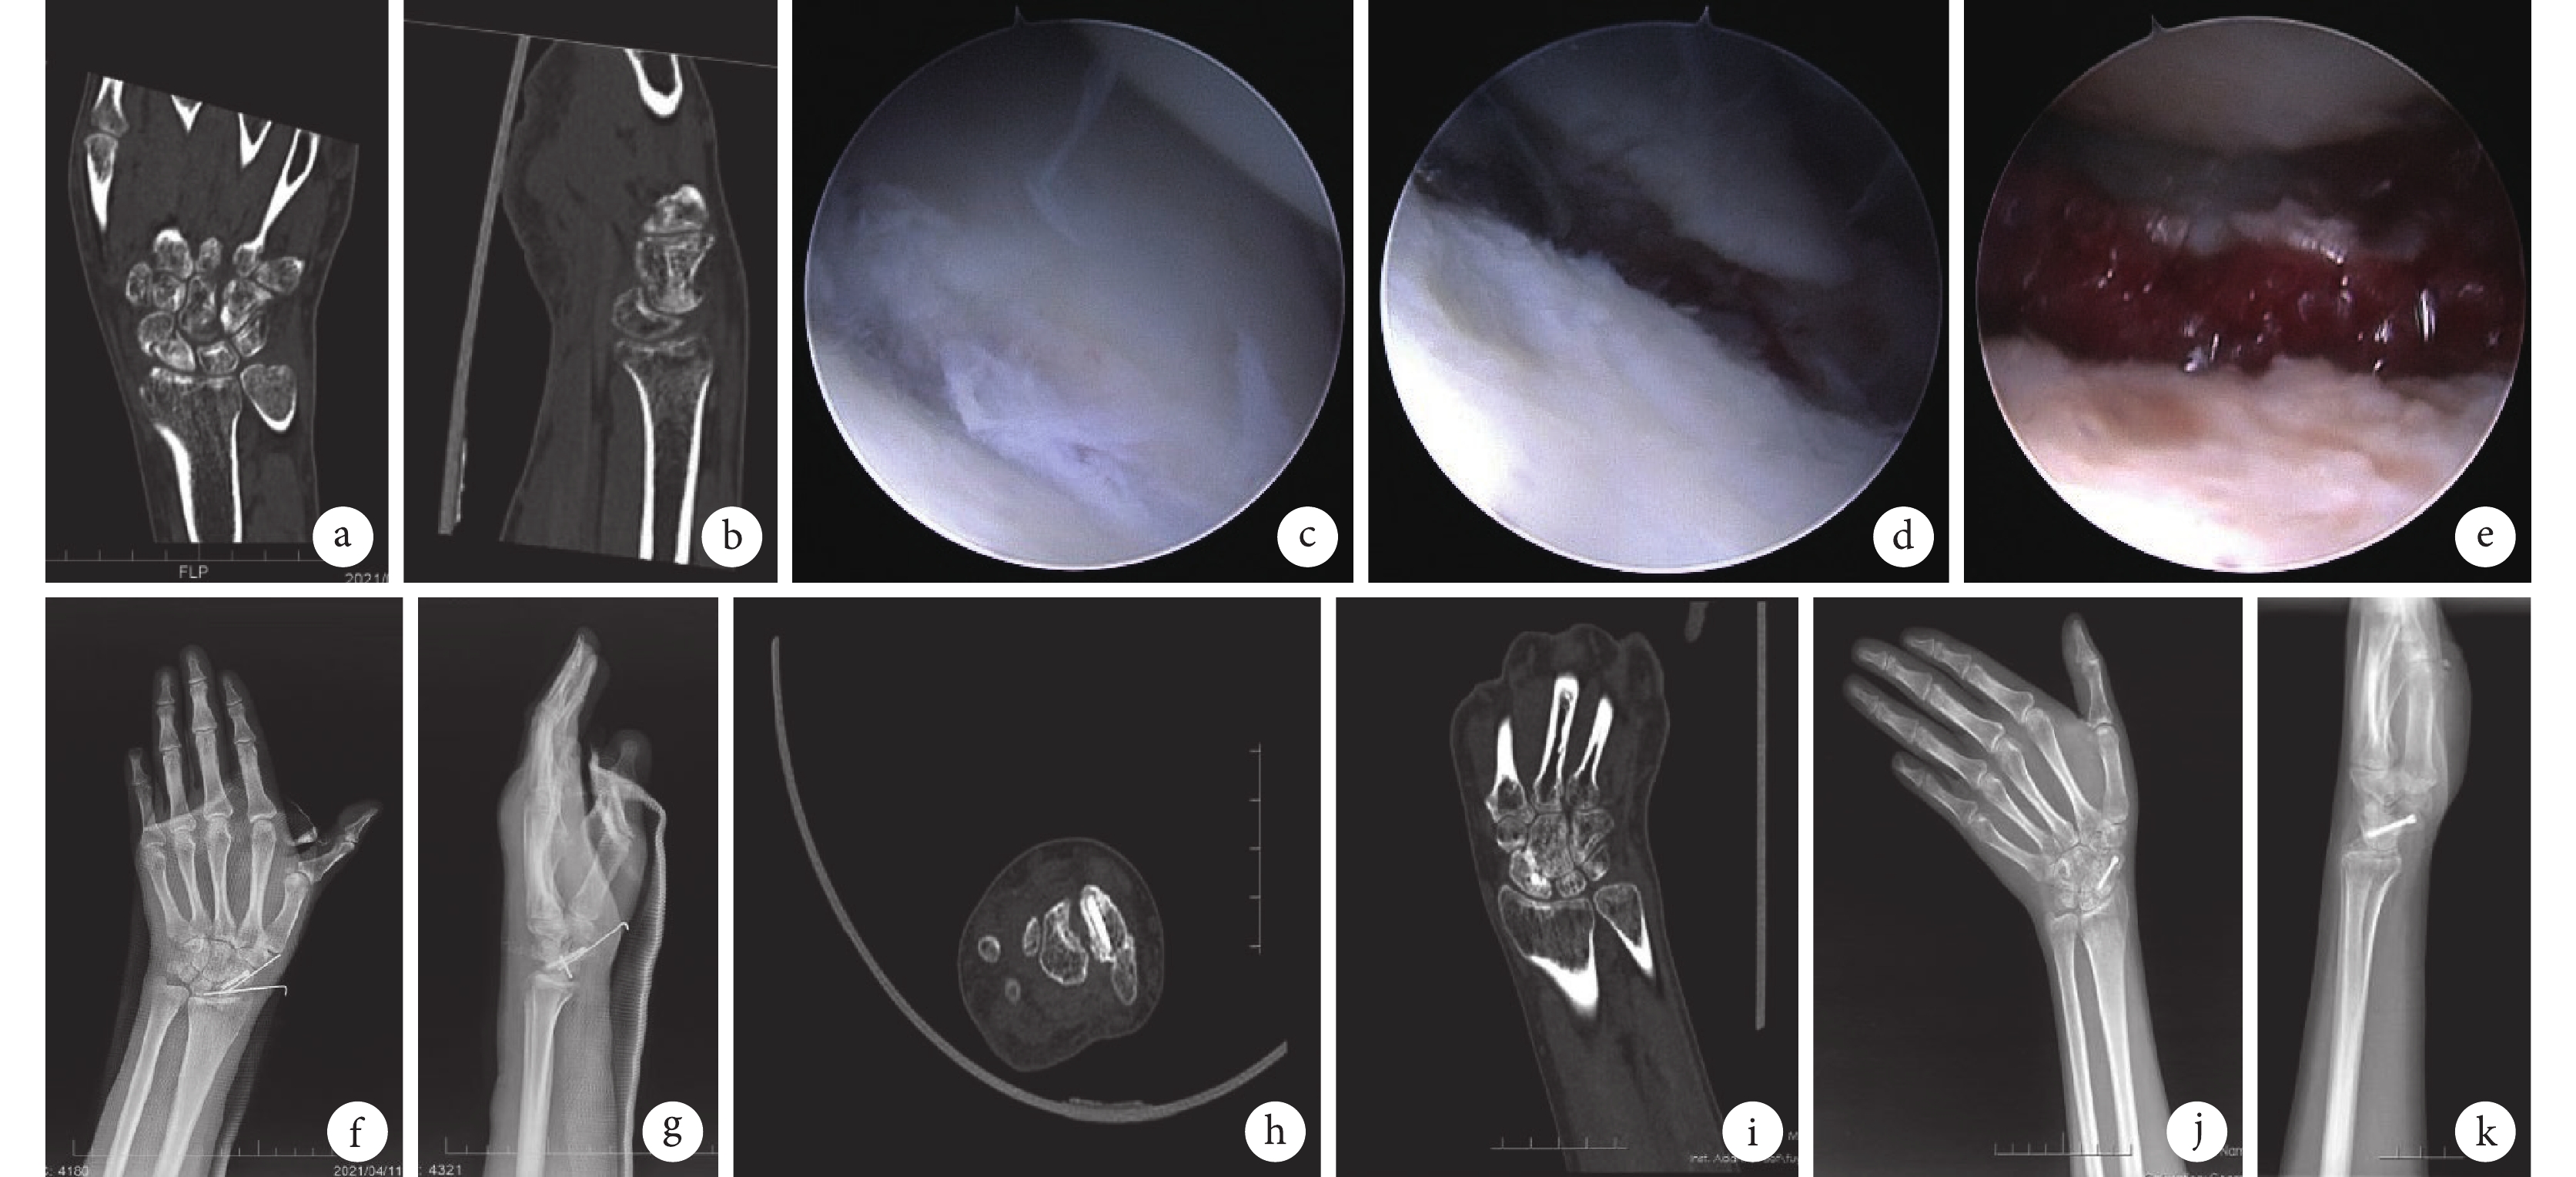

患者,男,42歲,左腕舟骨骨折不愈合(Slade-Geissler Ⅳ級)

a、b. 術前CT矢狀位及冠狀位示左腕舟骨骨折不愈合及DISI;c. 關節鏡下見腕舟骨骨折不愈合;d. 關節鏡下骨折端清創;e. 關節鏡下植入松質骨;f、g. 術后2周正側位X線片示骨折復位良好,植骨充分,內固定可靠;h、i. 術后4個月CT示骨折愈合;j、k. 術后8個月正側位X線片示骨折愈合良好

Figure1. A 42-year-old male patient with left scaphoid fracture nonunion (Slade-Geissler grade Ⅳ)a, b. Preoperative sagittal and coronal CT showed nonunion and dorsal intercalated segment instability of the left scaphoid fracture; c. Scaphoid fracture nonunion under arthroscopy; d. Arthroscopic debridement of fracture; e. Arthroscopic cancellous bone implantation; f, g. Anteroposterior and lateral X-ray films at 2 weeks after operation showed that the reduction of scaphoid fracture was good, bone grafting was sufficient, and internal fixation was reliable; h, i. CT at 4 months after operation showed fracture healing; j, k. Anteroposterior and lateral X-ray films at 8 months after operation showed good fracture healing